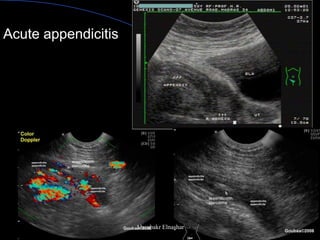

Scan RLQ with increasing pressure

to push bowel loops away

Empty cecum of gas& fluid

Sonographic Criteria

Noncompressible

> 7mm diameter

<6mm rules out appendicitis

Mural thickening > 3mm

Presence of appendicalith

Acute appendicitis